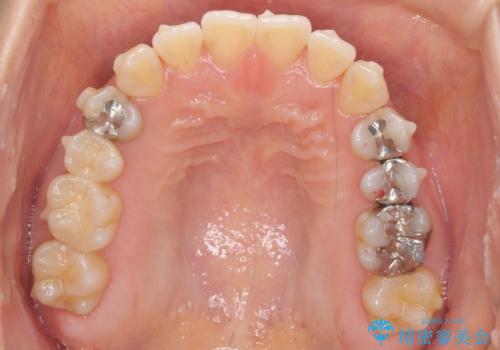

前歯のがたつき 若干受け口 インビザラインで

治療症例の内容

- 前歯のねじれおよび下の前歯が前に出ていることを気にして来院。

インビザラインで治療をおこないました。

前歯のねじれもなおり、比較的短期間でご満足いただけました。

部分矯正コースでしたので左下67の段差は特に治しておりません。

右下567及び左下6の虫歯治療も一緒に行っています。